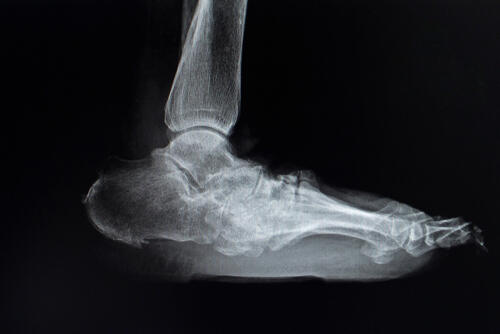

The case study, presented by Ravnik Singh, DPM, and Lawrence Fallat, DPM, FACFAS, focused on a 36-year-old male with diabetic peripheral neuropathy who had been experiencing ankle pain for 5 previous years. Radiographs showed severe collapse of the talar body, advanced degeneration and osteophyte formation of the ankle and subtalar joint, and asymmetric joint space narrowing.

The patient underwent tibio-talo-calcaneal arthrodesis with a femoral head allograft and intermetatarsal nail, gastrocnemius recession and external fixation. The authors noted the patient had routine follow-up for 10 years and has “expressed incredible gratitude as it was the first time he appreciated a straight leg and foot in years.” Authors added that the patient after 10 years had no pain, complications or deformity recurrence.